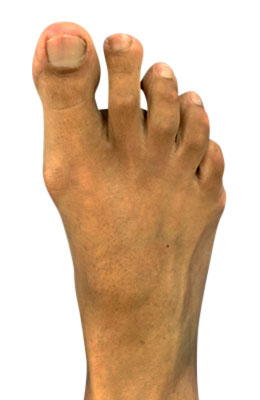

Minimally Invasive Bunion Surgery featuring the miniBunon™ System and Tailors Bunionectomy

Melissa is a 32-year-old businesswoman who could not be off her foot post-surgery, yet she had a severely painful bunion. We performed our miniBunon™ System (our trademarked minimally invasive bunion surgery) and had a dramatic correction with no downtime. Melissa continued to work after her bunion surgery and was back in shoes and full activity at 5 weeks. Melissa could not believe the results of her Bunionectomy resulting in no bony bump, no scar and amazing motion. “After” picture taken immediately following surgery. Note the bunion and bunionette (Tailor’s bunion) in the before picture.